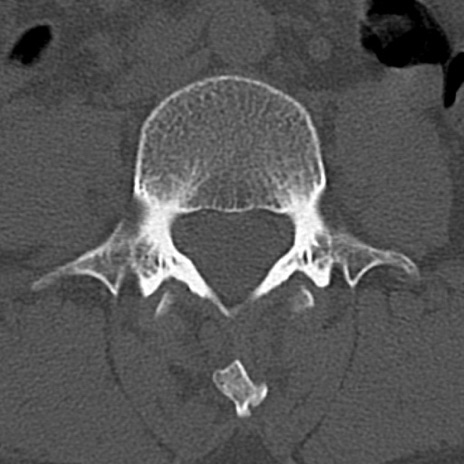

【整形】TIPS症例4 腰椎CT(横断像)

腰椎CT

横断像と矢状断像